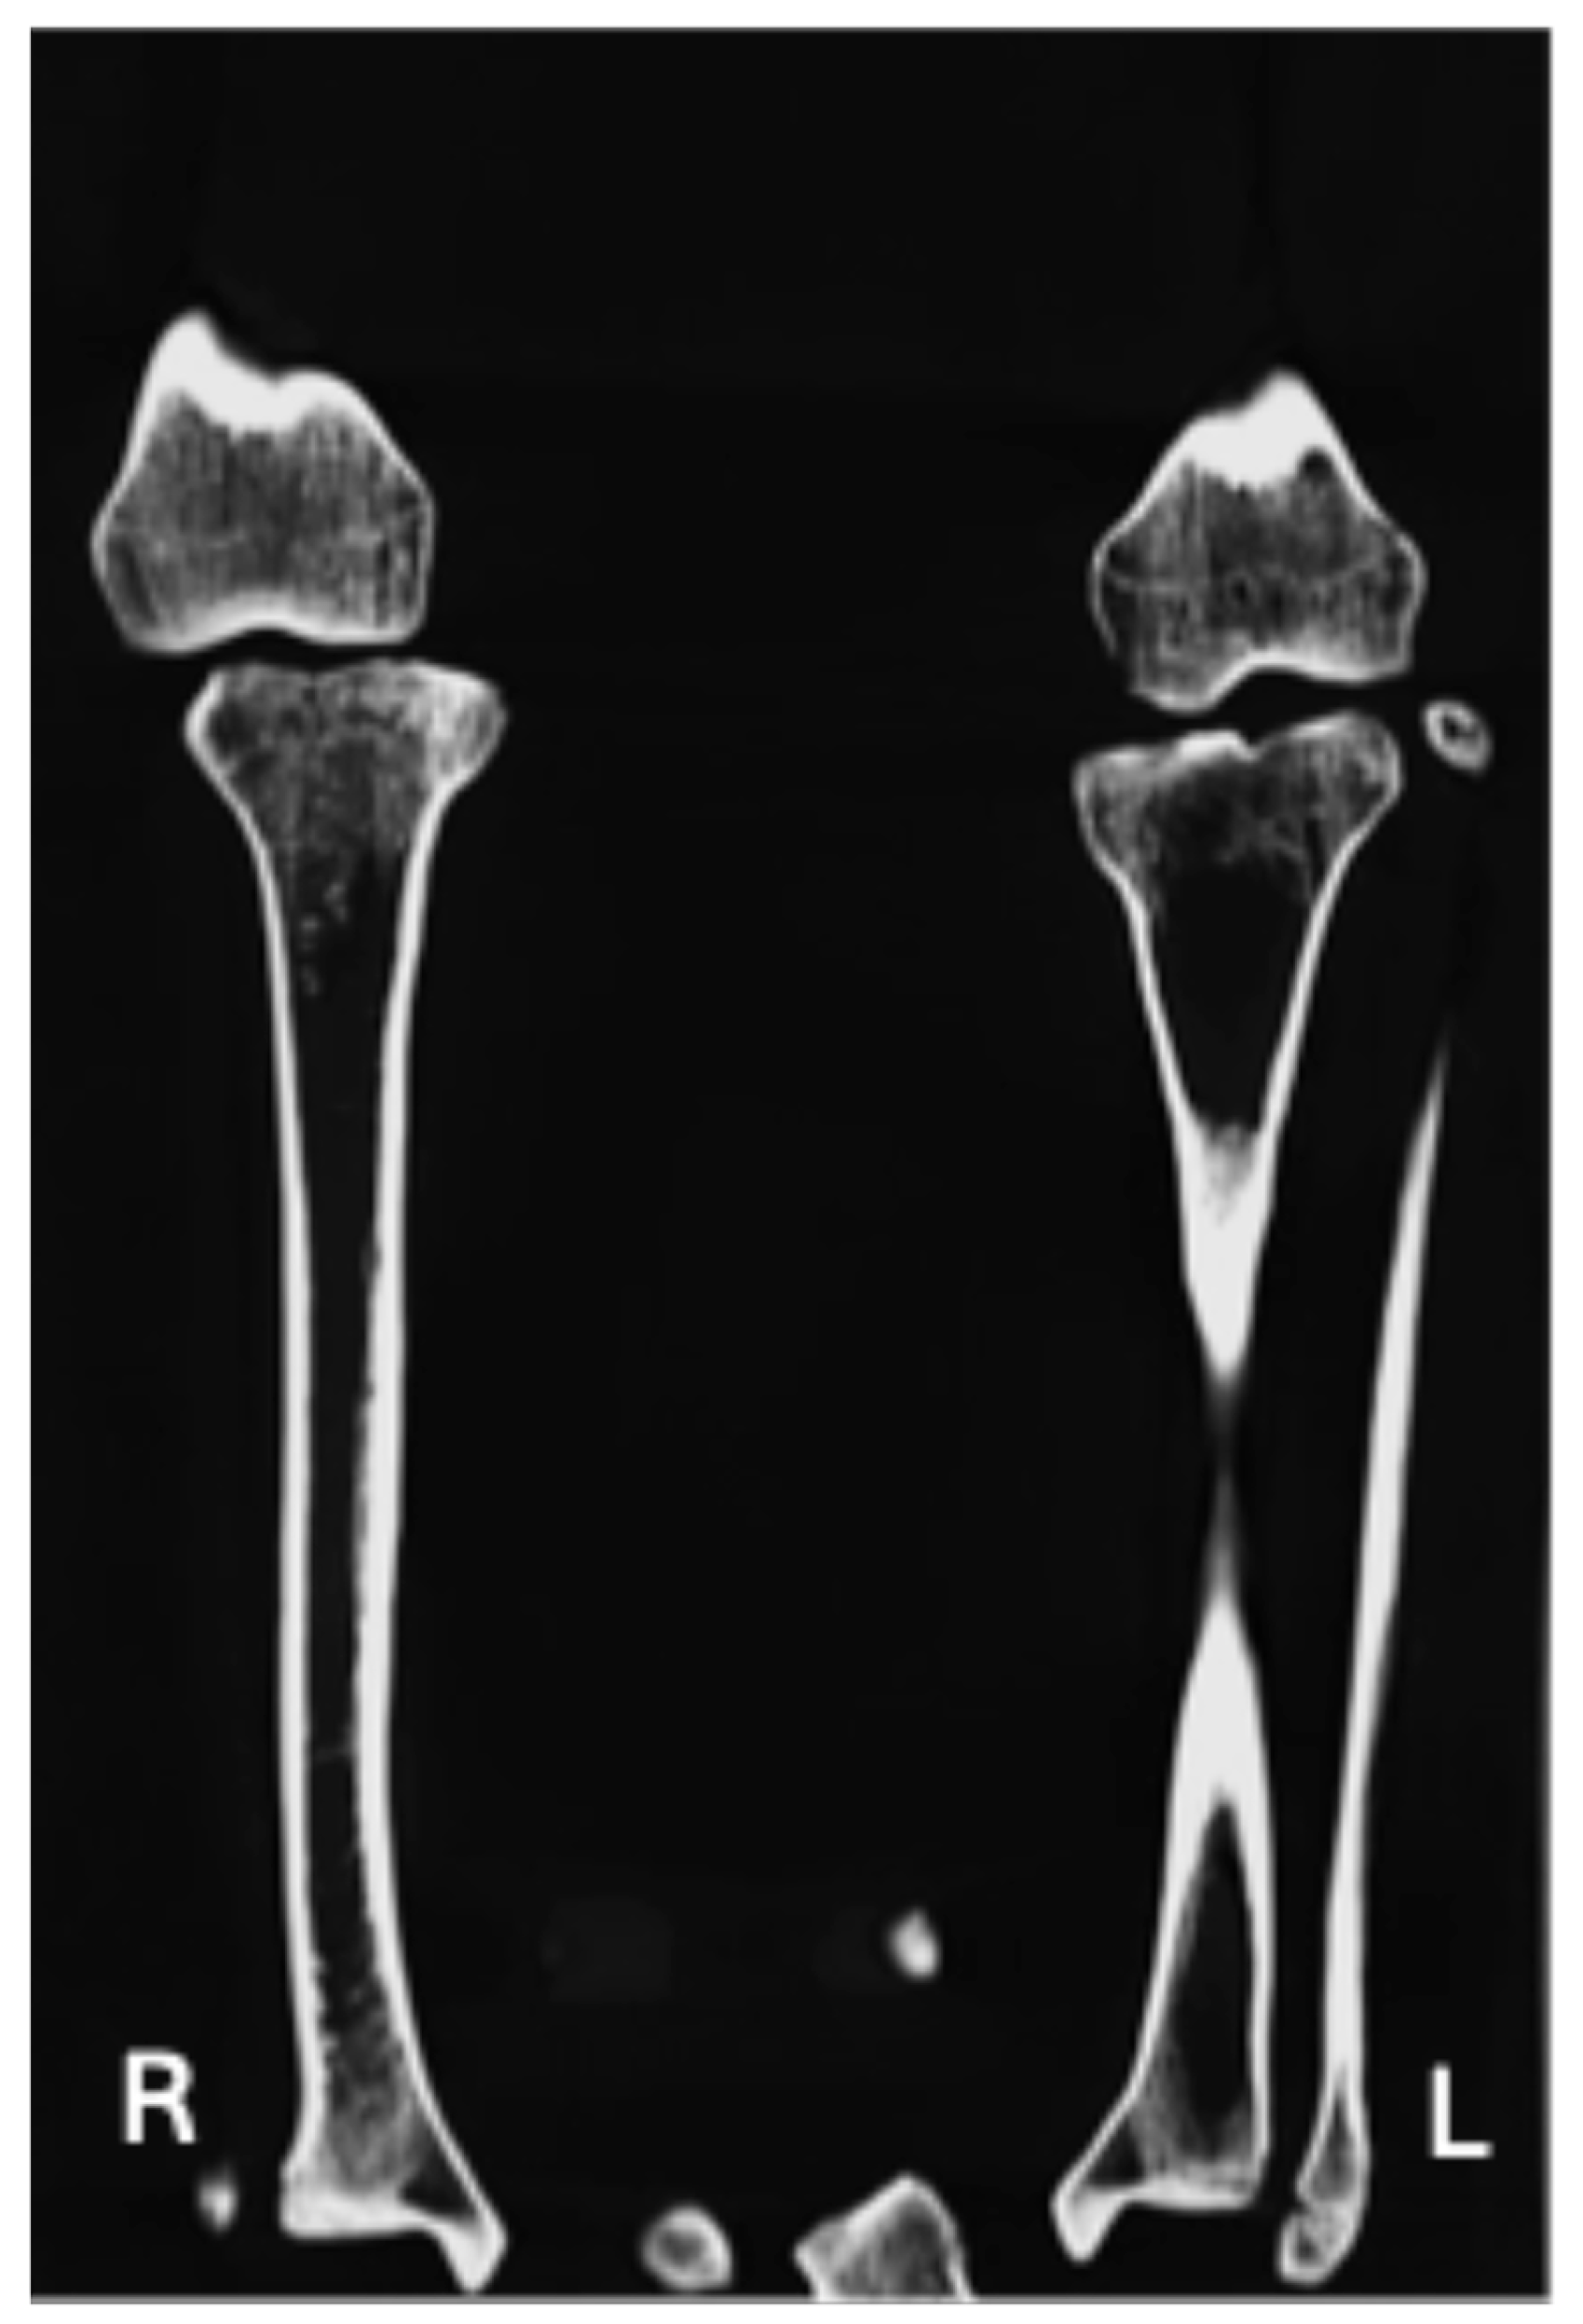

| Contralateral hip joint is definitively unaffected (Figure 4 and Figure 5) | X | X |

| Periarticular osteoporosis (Figure 4) | X | |

| Subchondral sclerosis (Figure 4) | X | |

| Lack of development of the intertrochanteric crest (Figure 2a and Figure 4) | X | X |

| Lack of development of the trochanteric fossa (Figure 2a and Figure 4) | X | X |

| Occult fractures (Figure 4) | X | |

| Triangular: the base facing the obturator foramen and the apex was directed postero-superiorly | Type 1 [32]: smooth shallow depression as articular surface developed just around the AIIS area, which was shifted laterally | Head: hypoplastic/aplastic | Subchondral sclerosis occurring at the knee joint margins |

| Extremely shallow and flatted | Head: Articular facet on the top for an altered joint architecture for the hip bone | Both medial and lateral joint erosion on the tibial plate bilaterally, particular in the left joint. | |

| Change in the posterodistal area, leading to the shifting of the spine of ischium antero-laterally | Trochanteric fossa not developed | ||

| Flat groove for the Obturator Externus | Intertrochanteric crest not fully developed | ||

| Wide acetabular notch | Uppermost attachment area for Vastus Lateralis as a flat spike | ||

| Inverted limbus | Shortening of the bone | ||

| No smooth articulating surface |